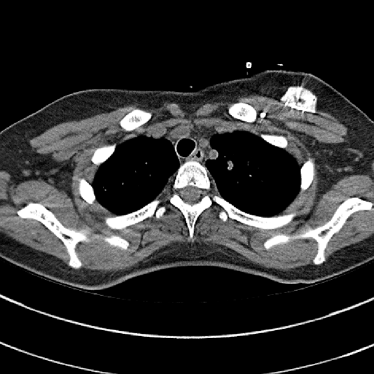

Refer to caption(a) Clinical Standard IRRefer to caption(a) Clinical Standard IR

Refer to caption(b) JENGRefer to caption(b) JENG

Refer to caption(c) Clinical Standard IRRefer to caption(c) Clinical Standard IR

Refer to caption(d) JENGRefer to caption(d) JENG

Figure 14: Qualitative clinical results from a thoracic CT staging dataset for a 12-year-old with osteosarcoma with pulmonary metastases. The clinical standard hybrid IR is shown on the left and JENG is on the right. (a) The clinical standard hybrid IR in lung window with a window center of -600 HU and a window width of 1500 HU. (b) JENG at a resolution comparable to the clinical standard, but with less noise and fewer artifacts. (c) The clinical standard hybrid IR in soft tissue window with a window center of 55 HU and a window width of 440 HU. A metastatic lung cancer nodule can be found in the left upper lobe. (d) JENG in soft tissue window at a comparable resolution, but with less noise and fewer artifacts. Note that JENG is not fully corrected for beam hardening artifacts.